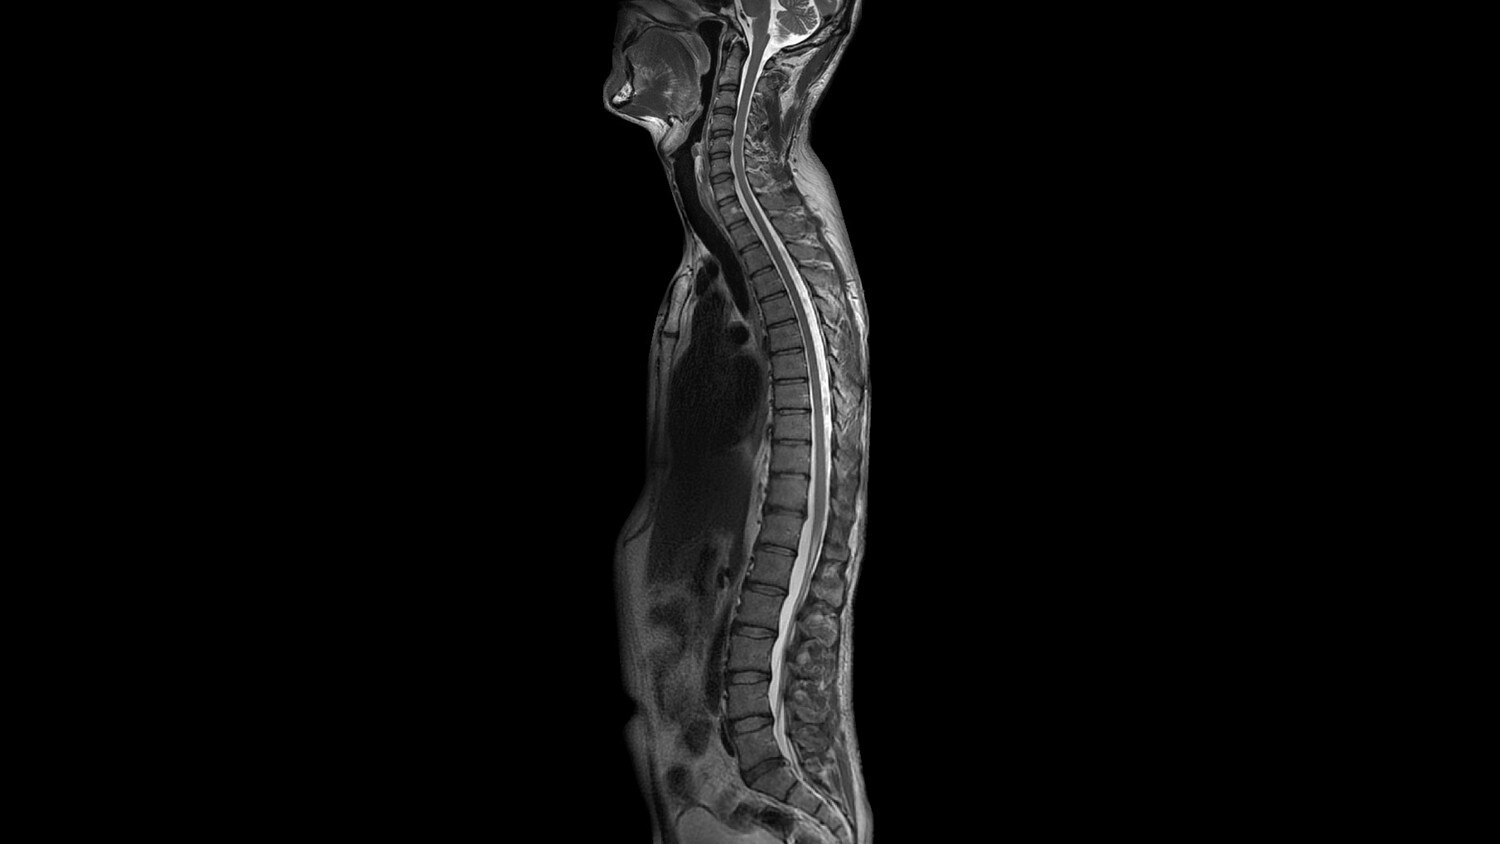

Magnet A new, light-weight magnet with a compact footprint that supports a 70 cm patient gantry and offers a large 50 x 50 x 50 cm useable field of view with excellent homogeneity for uncompromised coverage and quality.

MultiDrive RF Transmit Fully automated and independent RF pulse amplitude and phase control produce consistently clear 3.0T images.

OpTix Optical RF offers high channel count, analog to digital-optical signal conversion where it matters—inside the scan room to minimize noise and signal degradation, but away from the patient.

Gradients and RF body coils are water and air-cooled for optimum duty-cycle performance, short repetition time (TR) and echo time (TE), producing sharp and clear images.

Intuitive applications help clinicians utilize the full potential of 3.0T MR imaging.

GEM Posterior Array - Embedded high-density posterior array with optimal coil element geometry that enhances spine, abdomen, cardiac, and lower extremity scanning.